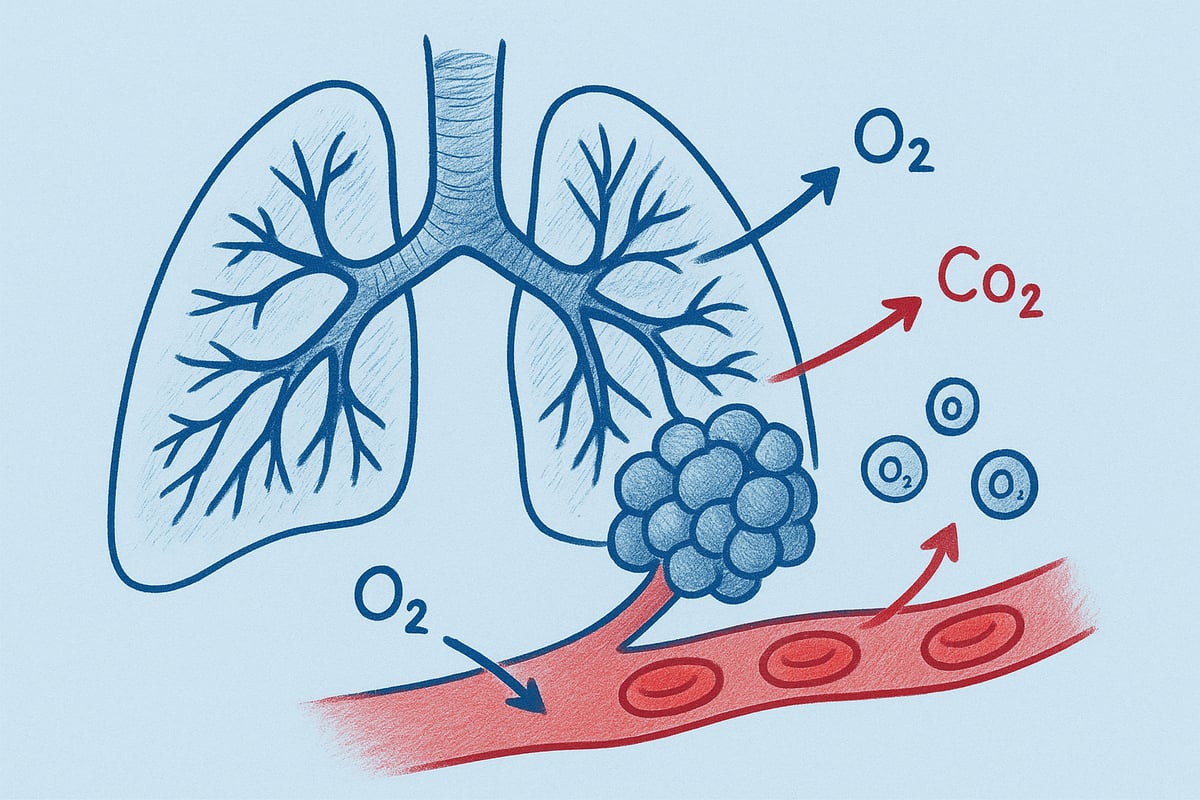

Blodkar og gasudveksling

Lungerne er tæt forbundet med kredsløbet gennem et fintmasket net af kapillærer. Disse små blodkar omkranser alveolerne og muliggør udvekslingen af ilt og kuldioxid mellem blodet og indåndingsluften.

Når vi indånder, passerer ilt gennem alveolevæggene og over i blodet, hvor det bindes til hæmoglobin. Samtidig transporteres kuldioxid fra blodet ud i alveolerne for at blive udåndet. Denne proces er grundlaget for, sådan fungerer lungerne, og den er afgørende for kroppens energiproduktion.

Ifølge Sundhedsstyrelsen kan en voksen i hvile optage op til 250 ml ilt i minuttet. Kapaciteten afhænger af alder, helbred og fysisk aktivitet. En effektiv gasudveksling sikrer, at kroppen får den nødvendige ilt, og at affaldsstoffer fjernes hurtigt.

Når du trækker vejret ind, starter en fascinerende rejse for ilten. Inde i lungerne passerer ilten gennem de fine vægge i alveolerne og over i blodet. Her binder ilten sig hurtigt til hæmoglobin, et protein i de røde blodlegemer, som fungerer som transportmiddel. På denne måde kan blodet fragte store mængder ilt effektivt ud til kroppens celler.

For at sætte det i perspektiv, tager det kun et par sekunder for ilten at bevæge sig fra lungerne til tåspidserne, når sådan fungerer lungerne optimalt. Dette skyldes det tætte netværk af blodkar, der omkranser alveolerne og sikrer hurtig udveksling. Hæmoglobinets evne til at binde og slippe ilt afhænger af kroppens behov, hvilket gør systemet yderst fleksibelt.

Kuldioxid og udskillelse

Samtidig med at ilt transporteres ud til kroppens celler, dannes kuldioxid som affaldsprodukt. Kuldioxid transporteres hovedsageligt i opløst form i blodet, men en mindre del bindes også til hæmoglobin. Herefter føres kuldioxiden tilbage til lungerne, hvor den udskilles med udåndingsluften.

Reguleringen af kuldioxid i blodet er essentiel for kroppens pH-balance. Hvis kuldioxid ophobes, bliver blodet surere, hvilket kan påvirke kroppens funktioner negativt. Derfor er det vigtigt, at sådan fungerer lungerne effektivt, så kuldioxiden fjernes hurtigt og balancen holdes.